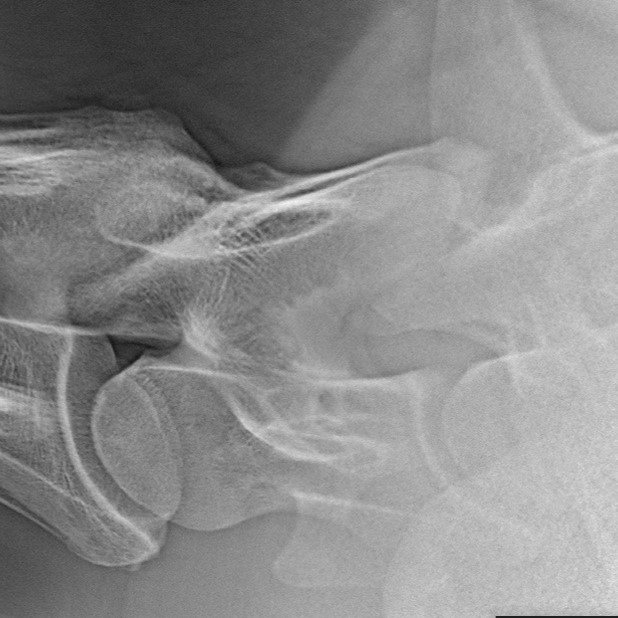

In Anbetracht bestehender Unsicherheit in der Beurteilung von Röntgenbildern der unteren Halswirbelsäule auch im Rahmen von Kaufuntersuchungen möchte die GPM mit einer Stellungnahme noch einmal auf den Stand der Wissenschaft gerade auch als Grundlage einer rechtlichen Beurteilung hinweisen.

In Anbetracht bestehender Unsicherheit in der Beurteilung von Röntgenbildern der unteren Halswirbelsäule auch im Rahmen von Kaufuntersuchungen möchte die GPM mit einer Stellungnahme noch einmal auf den Stand der Wissenschaft gerade auch als Grundlage einer rechtlichen Beurteilung hinweisen. Die Stellungnahme finden Sie HIER.